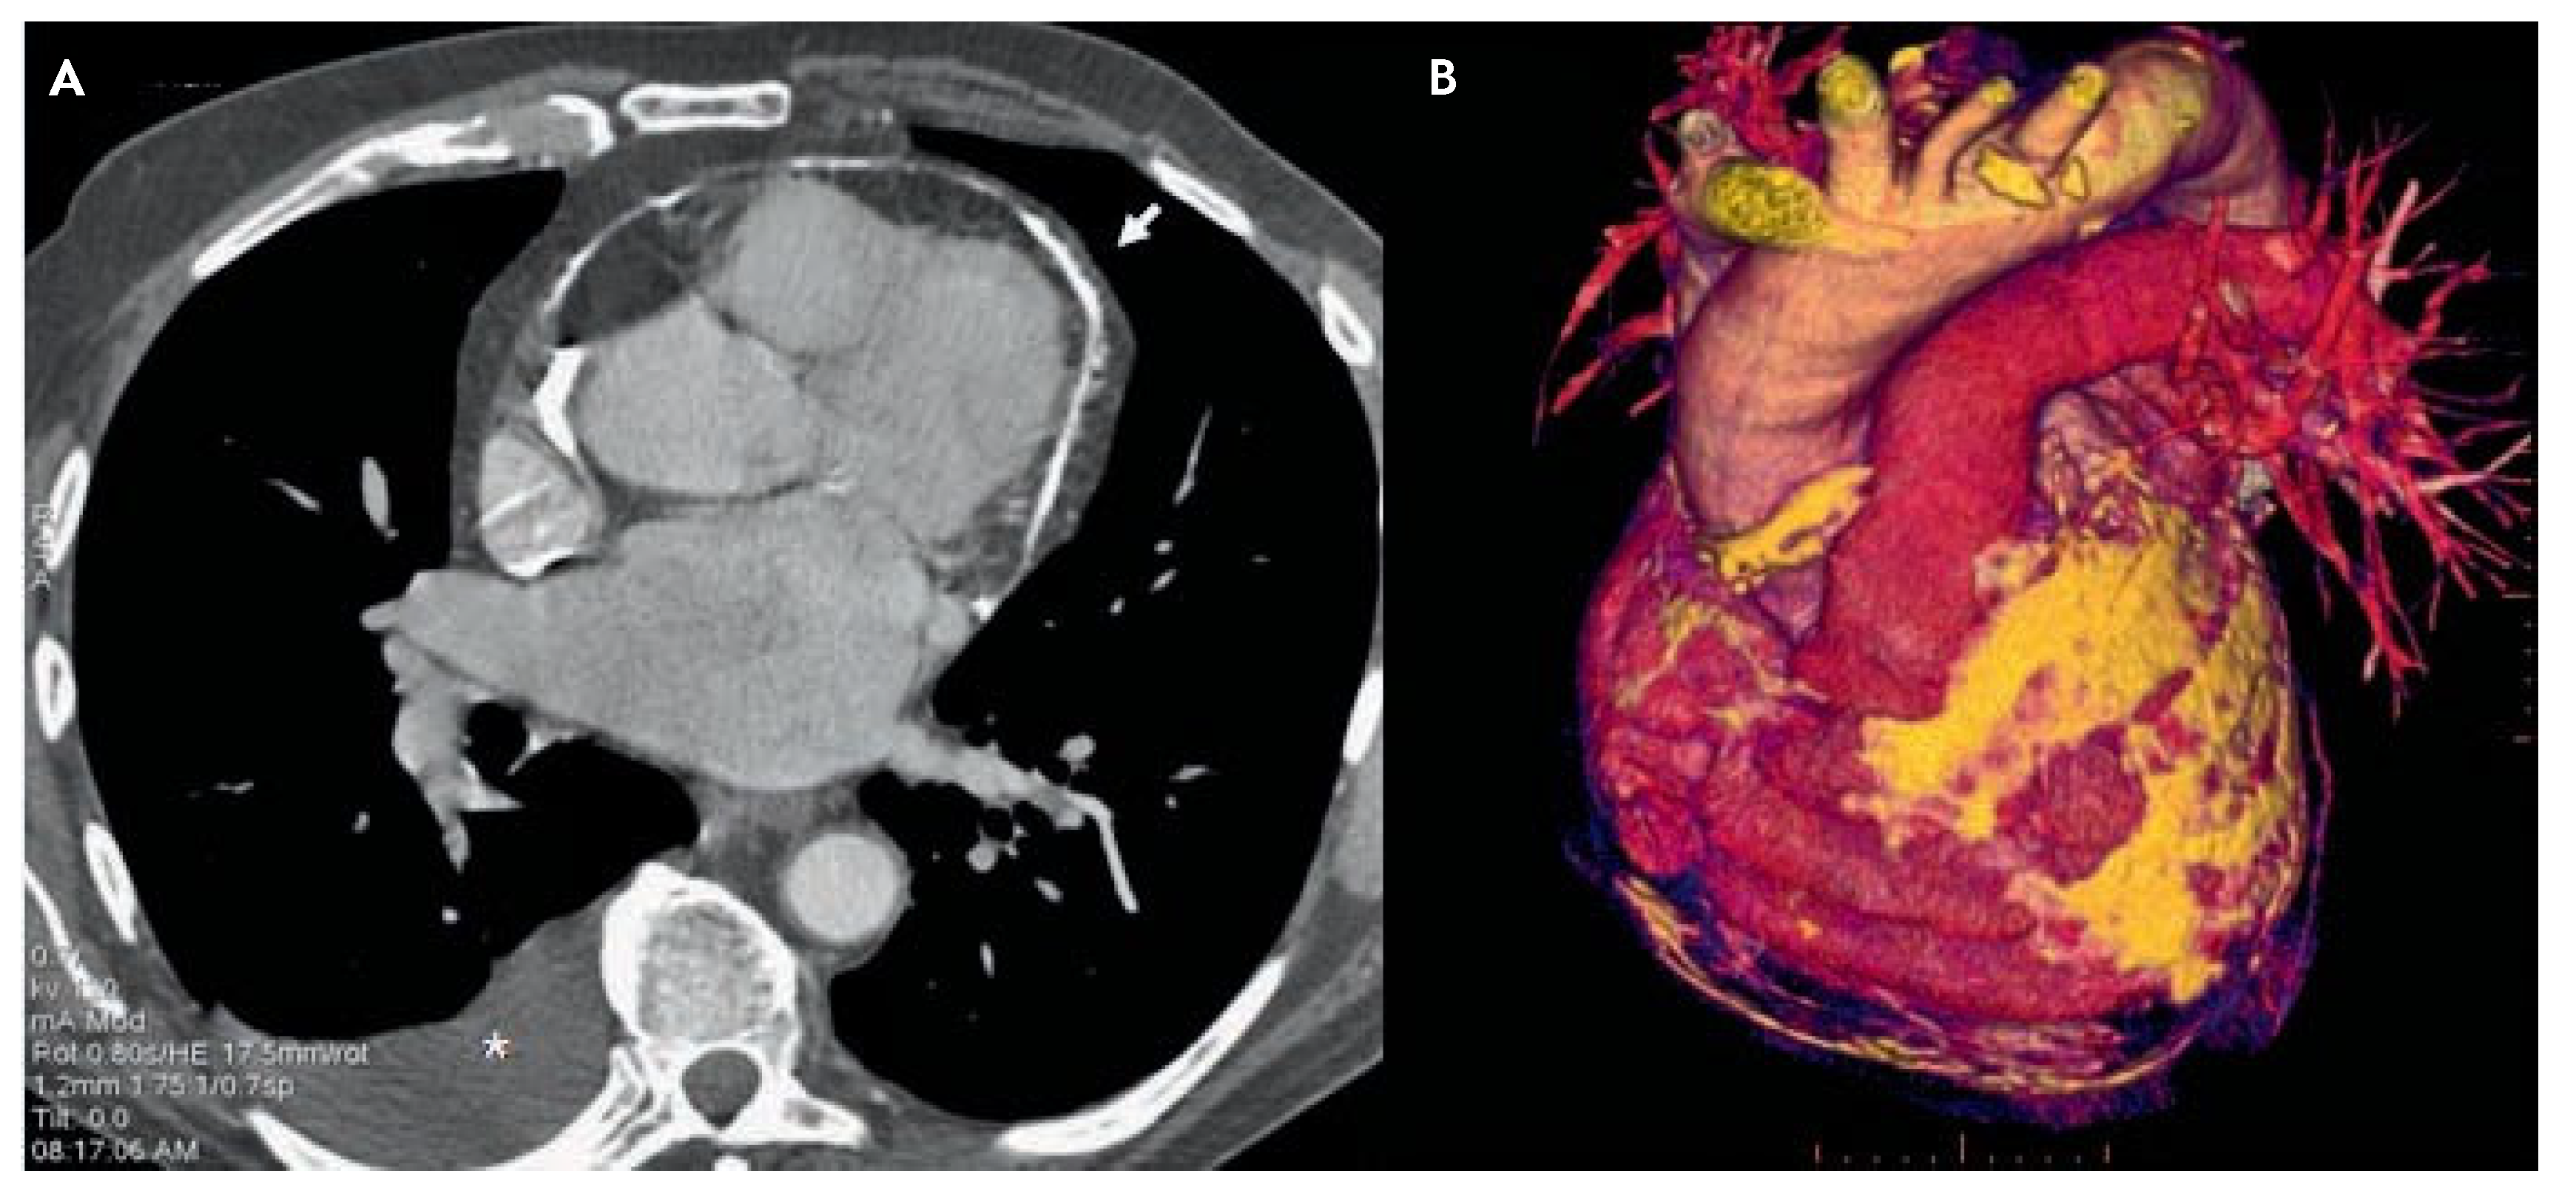

Chest X-ray (Figure 1A,B) shows diffuse pericardial calcifications and right pleural effusion. Thoracic CT scan confirms pleural effusion and circumferential pericardial thick-ening (6 mm) with calcifications (fig. 2A) together with dilatation of the inferior vena cava, hepatomegaly and ascites. 3-dimensional reconstruction (Figure 2B) nicely delineates the spatial extension of pericardial calcifications.

Figure 2. Standard chest CT scan after contrast media injection. A transverse section (1.2 mm thickness) at the aortic root level showing circumferential pericardial calcification (arrow) and right pleural effusion (*). B 3D reconstruction of the heart and great vessels (anterior view) demonstrating calcifications of the pericardium (in yellow) covering most of the antero-lateral wall of the left ventricle.